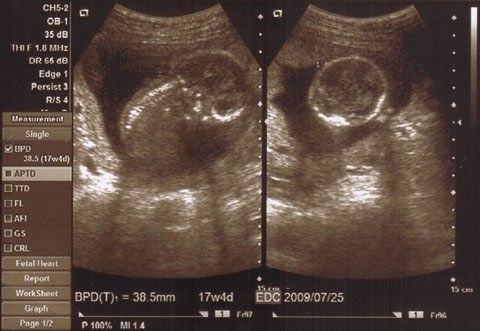

5ヶ月の健診に行きました。

手が頭の横にあって、

どんどん人間らしくなってるのがわかりました。

心臓もしっかり動いていて、

予想以上に大きい我が子にちょっと感動。

予定日は8月3日なのに、

豆太郎の大きさは7月25日に生まれてくる大きさみたい。

・・・うちの子でかっっ(笑